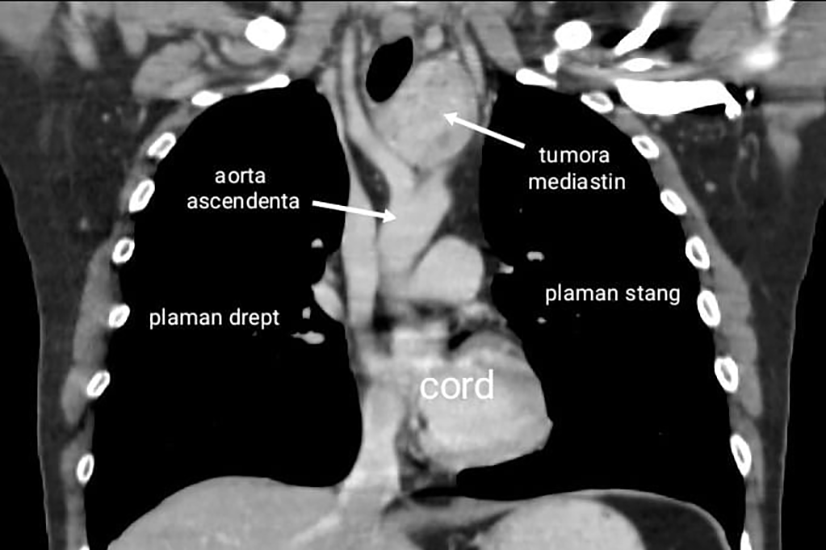

Andrei, aparent sanatos si fara istoric medical semnificativ, a fost infectat cu SARS-CoV-2, iar pentru ca simtea ca nu respira bine si pentru a exclude o posibila pneumonie, s-a orientat catre investigatii imagistice. Examenul CT toracic a evidentiat la nivel mediastinal (zona dintre cei doi plamani) o formatiune tumorala de mari dimensiuni, situata intre arterele mari mediastinale .

Formatiunea voluminoasa de 7 centimetri se intindea de la stern la coloana vertebrala, deplasand spre dreapta traheea si esofagul si era pozitionata intre arterele mari mediastinale, ceea ce facea dificil accesul si extirparea acesteia in conditii de siguranta. Investigatiile au aratat ca tumora era o tiroida ectopica mediastinala nefunctionala, distincta de glanda tiroida normala, ceea ce reprezinta o anomalie extrem de rara, in literatura de specialitate fiind descrise doar cateva cazuri. Din cauza dimensiunilor mari, tiroida ectopica mediastinala trebuia rezecata, cu pastrarea pe loc a tiroidei cervicale normale.